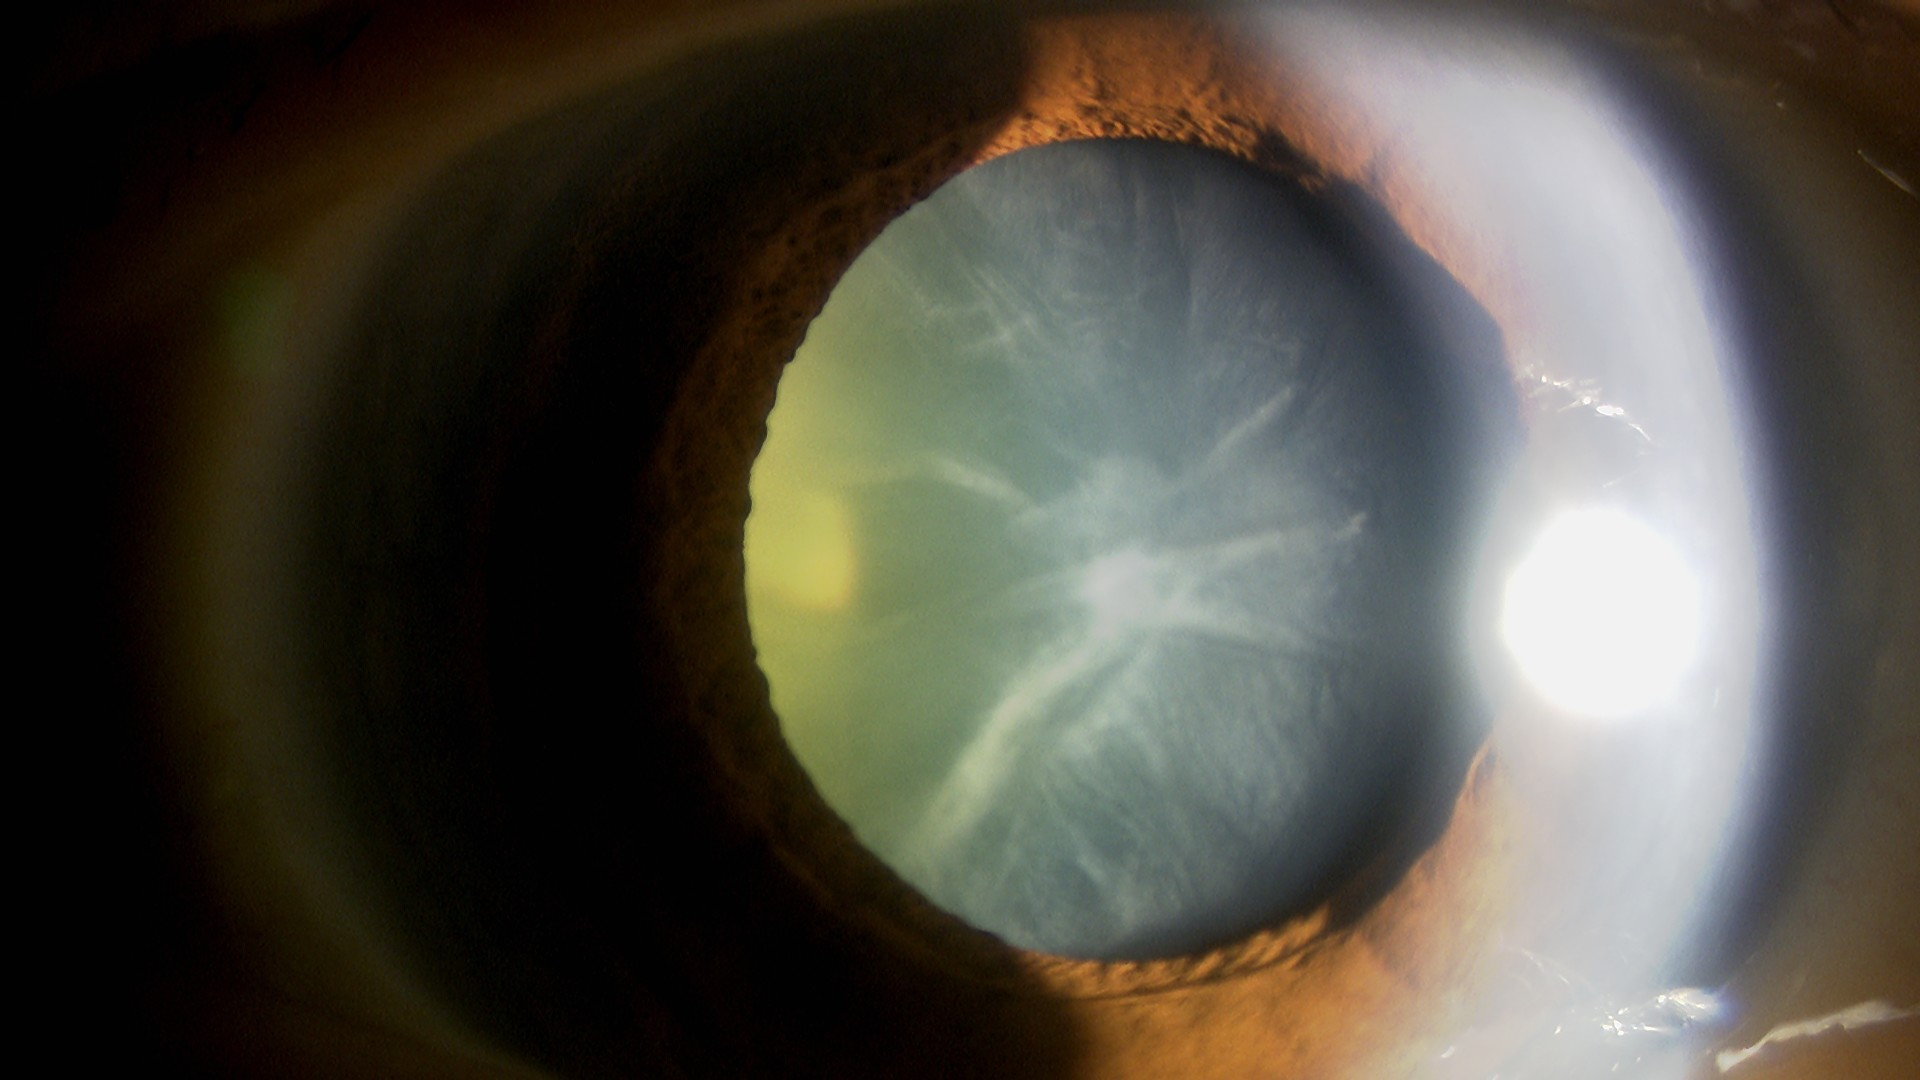

水晶体再建術

もともと遠視もあったため、運転する時も近くを見る時も眼鏡を使用していました。術後は運転も裸眼でばっちり見えるようになりました。40代半ばから老眼鏡を使用してきましたが、術後は老眼鏡がなくともスマートフォンや雑誌が見えるようになりました。ピアノの時にも眼鏡が必要ないので楽になったとのことです。夜間のハローグレアは出ますが、運転には支障がないとのことです。